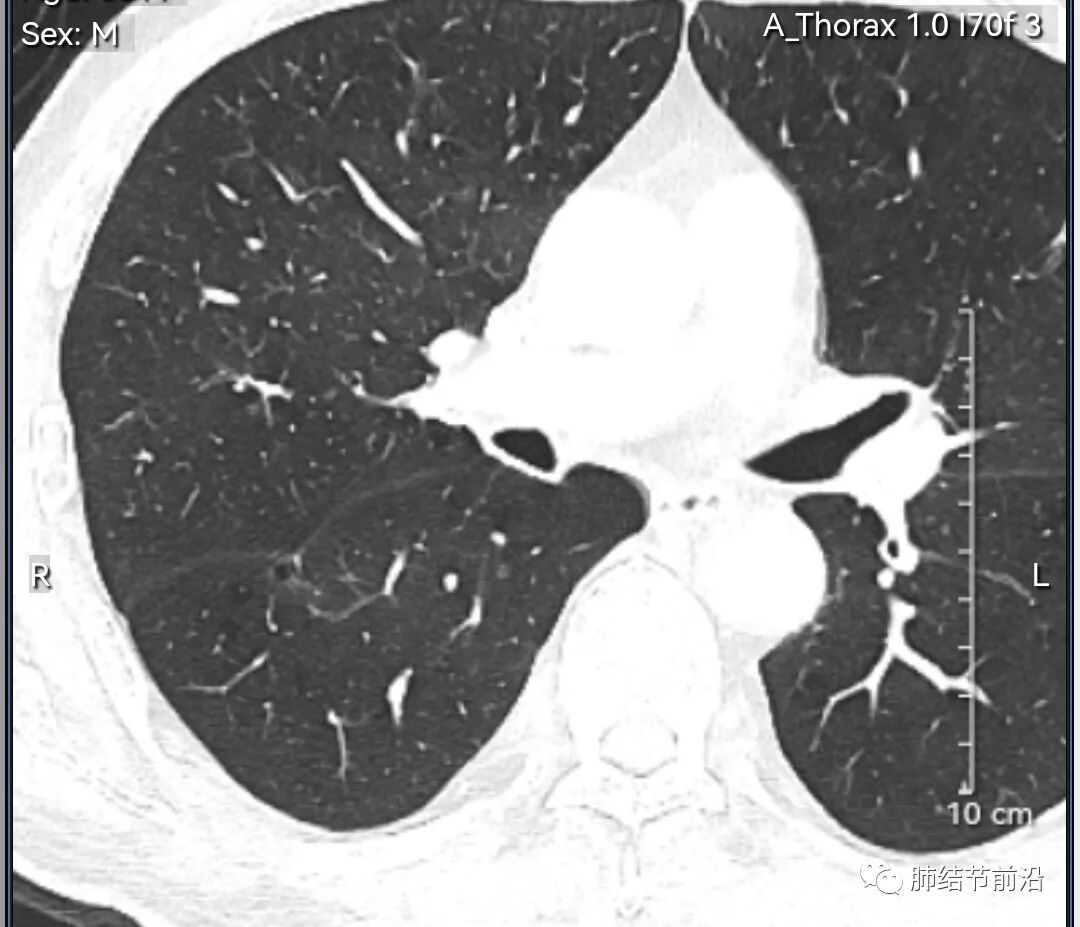

男性,67岁,重度吸烟史。CT发现右下肺囊腔。来看一下这个CT的特点:

该囊腔形态非常有特点,和常见的圆形肺大泡有很大的区别。

1.囊腔中央实性成分,周围有磨玻璃影。

2.囊腔中央有血管。

3.囊腔外周有分叶形态。

4.囊腔有胸膜牵拉。

出现这几种形态,CT可以确认恶性的腺癌。这个囊腔形成的机制,为肿瘤实性成分堵塞细支气管形成活瓣,肺泡内压力增高破裂行成,因此肺内血管成分保留。由于肺泡压力增高,而呈分叶状。另外,也有肿瘤的胸膜牵拉这一特点。

囊腔周围磨玻璃+囊腔中央血管为特征性表现。如果持续存在,几乎可以100%确认为早期肺腺癌。

建议患者手术切除,术后病理为浸润性腺癌,腺泡型,部分为实体型。IA1期,术后不用治疗。